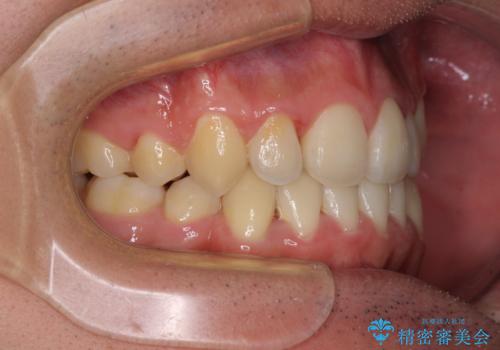

- 上下の八重歯や乱杭歯を気にして来院され患者様です。

スペースを確保するため、上下左右の小臼歯を抜歯し、ワイヤー装置に矯正することとしました。

奥歯の咬み合わせの左右差が大きかったため、変則的な抜歯矯正を行いました。

治療期間はやや長期化しましたが、満足のいく歯並びとなりました。